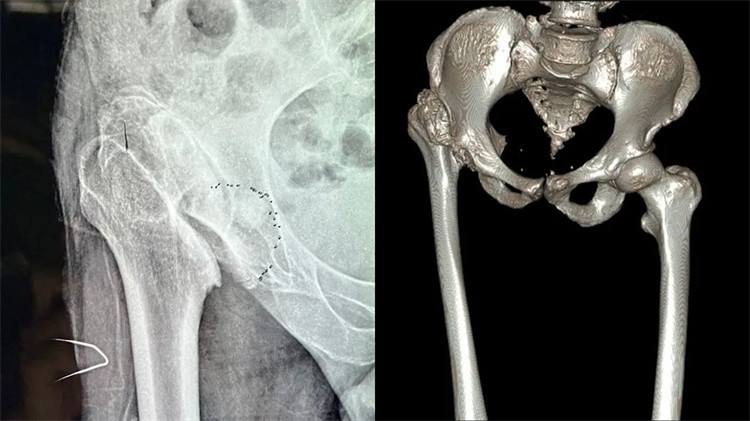

患者術(shù)前嚴(yán)重變形的髖關(guān)節(jié)

周大伯來(lái)院后經(jīng)X線片及CT檢查,發(fā)現(xiàn)右側(cè)股骨頭壞死、形態(tài)失常,已經(jīng)完全脫離正常的位置,且很難找到真臼,右側(cè)髖臼形態(tài)失常、部分骨質(zhì)缺失。想要徹底解決周大伯的問(wèn)題,需要進(jìn)行右側(cè)人工全髖關(guān)節(jié)置換。但周大伯患病50余年,且有過(guò)失敗的手術(shù)病史,髖關(guān)節(jié)感染后遺癥,髖關(guān)節(jié)脫位,長(zhǎng)短腿5公分,手術(shù)難度系數(shù)較大,不能有任何偏差,稍有偏差,嚴(yán)重者可影響手術(shù)效果,留下后遺癥。

羅軍主任首先為周大伯進(jìn)行了CT掃描,將周大伯雙髖關(guān)節(jié)CT掃描數(shù)據(jù)傳輸?shù)?D打印機(jī),按照1:1的比例用3D技術(shù)“打印”了一個(gè)一模一樣的髖關(guān)節(jié)模型。該模型將周大伯的壞死關(guān)節(jié)及脫位程度和其他細(xì)節(jié)完美呈現(xiàn)。借助該模型,羅主任能“直觀”周大伯骨骼病變的三維立體結(jié)構(gòu),除了有助于制定詳細(xì)的手術(shù)預(yù)案外,還能利用模型進(jìn)行術(shù)前模擬截骨、固定,選擇好合適的人工髖關(guān)節(jié)假體及3D打印補(bǔ)塊,提前預(yù)演整個(gè)手術(shù)過(guò)程,預(yù)見(jiàn)復(fù)雜手術(shù)過(guò)程中可能出現(xiàn)的各類難題,從而提高了手術(shù)的精準(zhǔn)率,并大幅縮短了手術(shù)時(shí)間,更降低了手術(shù)風(fēng)險(xiǎn)、減少并發(fā)癥出現(xiàn)。